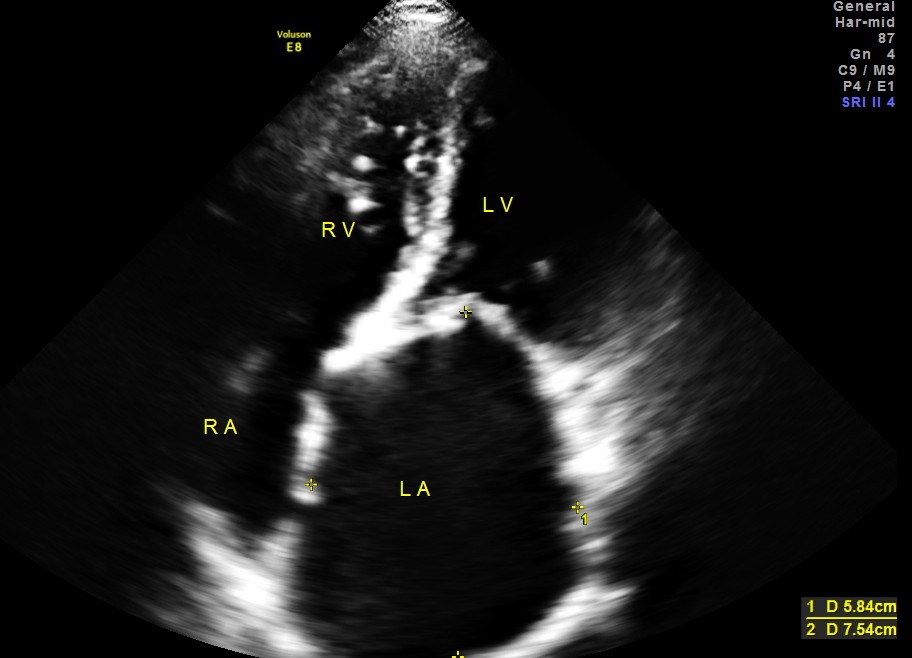

Her Echo cardiogram showed the following findings :

This patient had Rheumatic heart disease , moderate mitral stenosis with pulmonary hypertension .